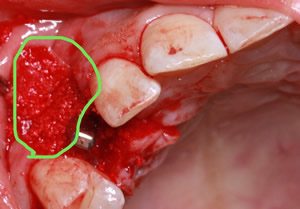

症例5

治療前

インプラント埋入時

治療後

- 年齢・性別

- 35歳男性

- 治療期間

- 3ヶ月

- 抜歯

- 右上1.3左上6.7の残根抜歯

- 治療費

- 123.2万円

- 備考

- 右上1.3左上6.7の欠損部

- 治療内容

- 4本のインプラントを一回のオペで埋入。

- 施術の副作用(リスク)

- オペによる知覚障害。インプラントによる歯肉炎。インプラント脱落。